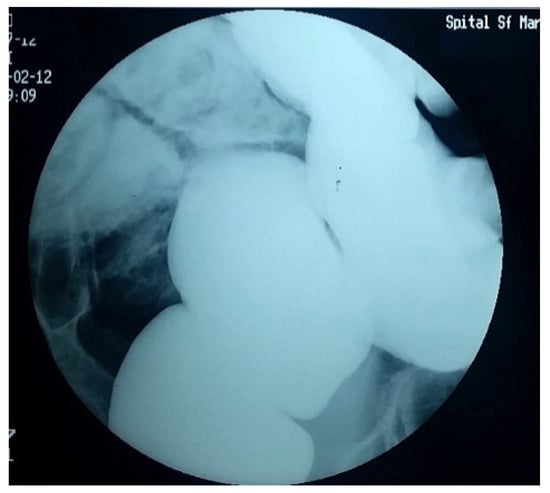

4. Diagnostic Criteria for the Acquired Megacolon